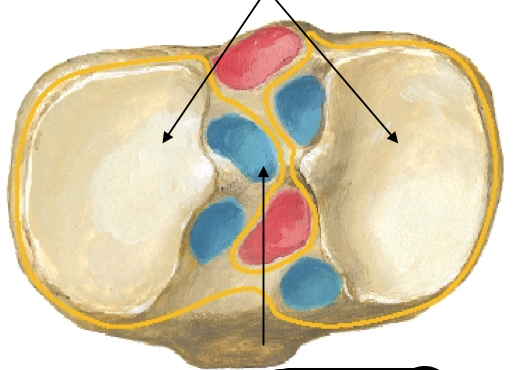

Where do the minisci of the knee sit?

tibial condyles

Menisci divide the joint cavity into two compartments: